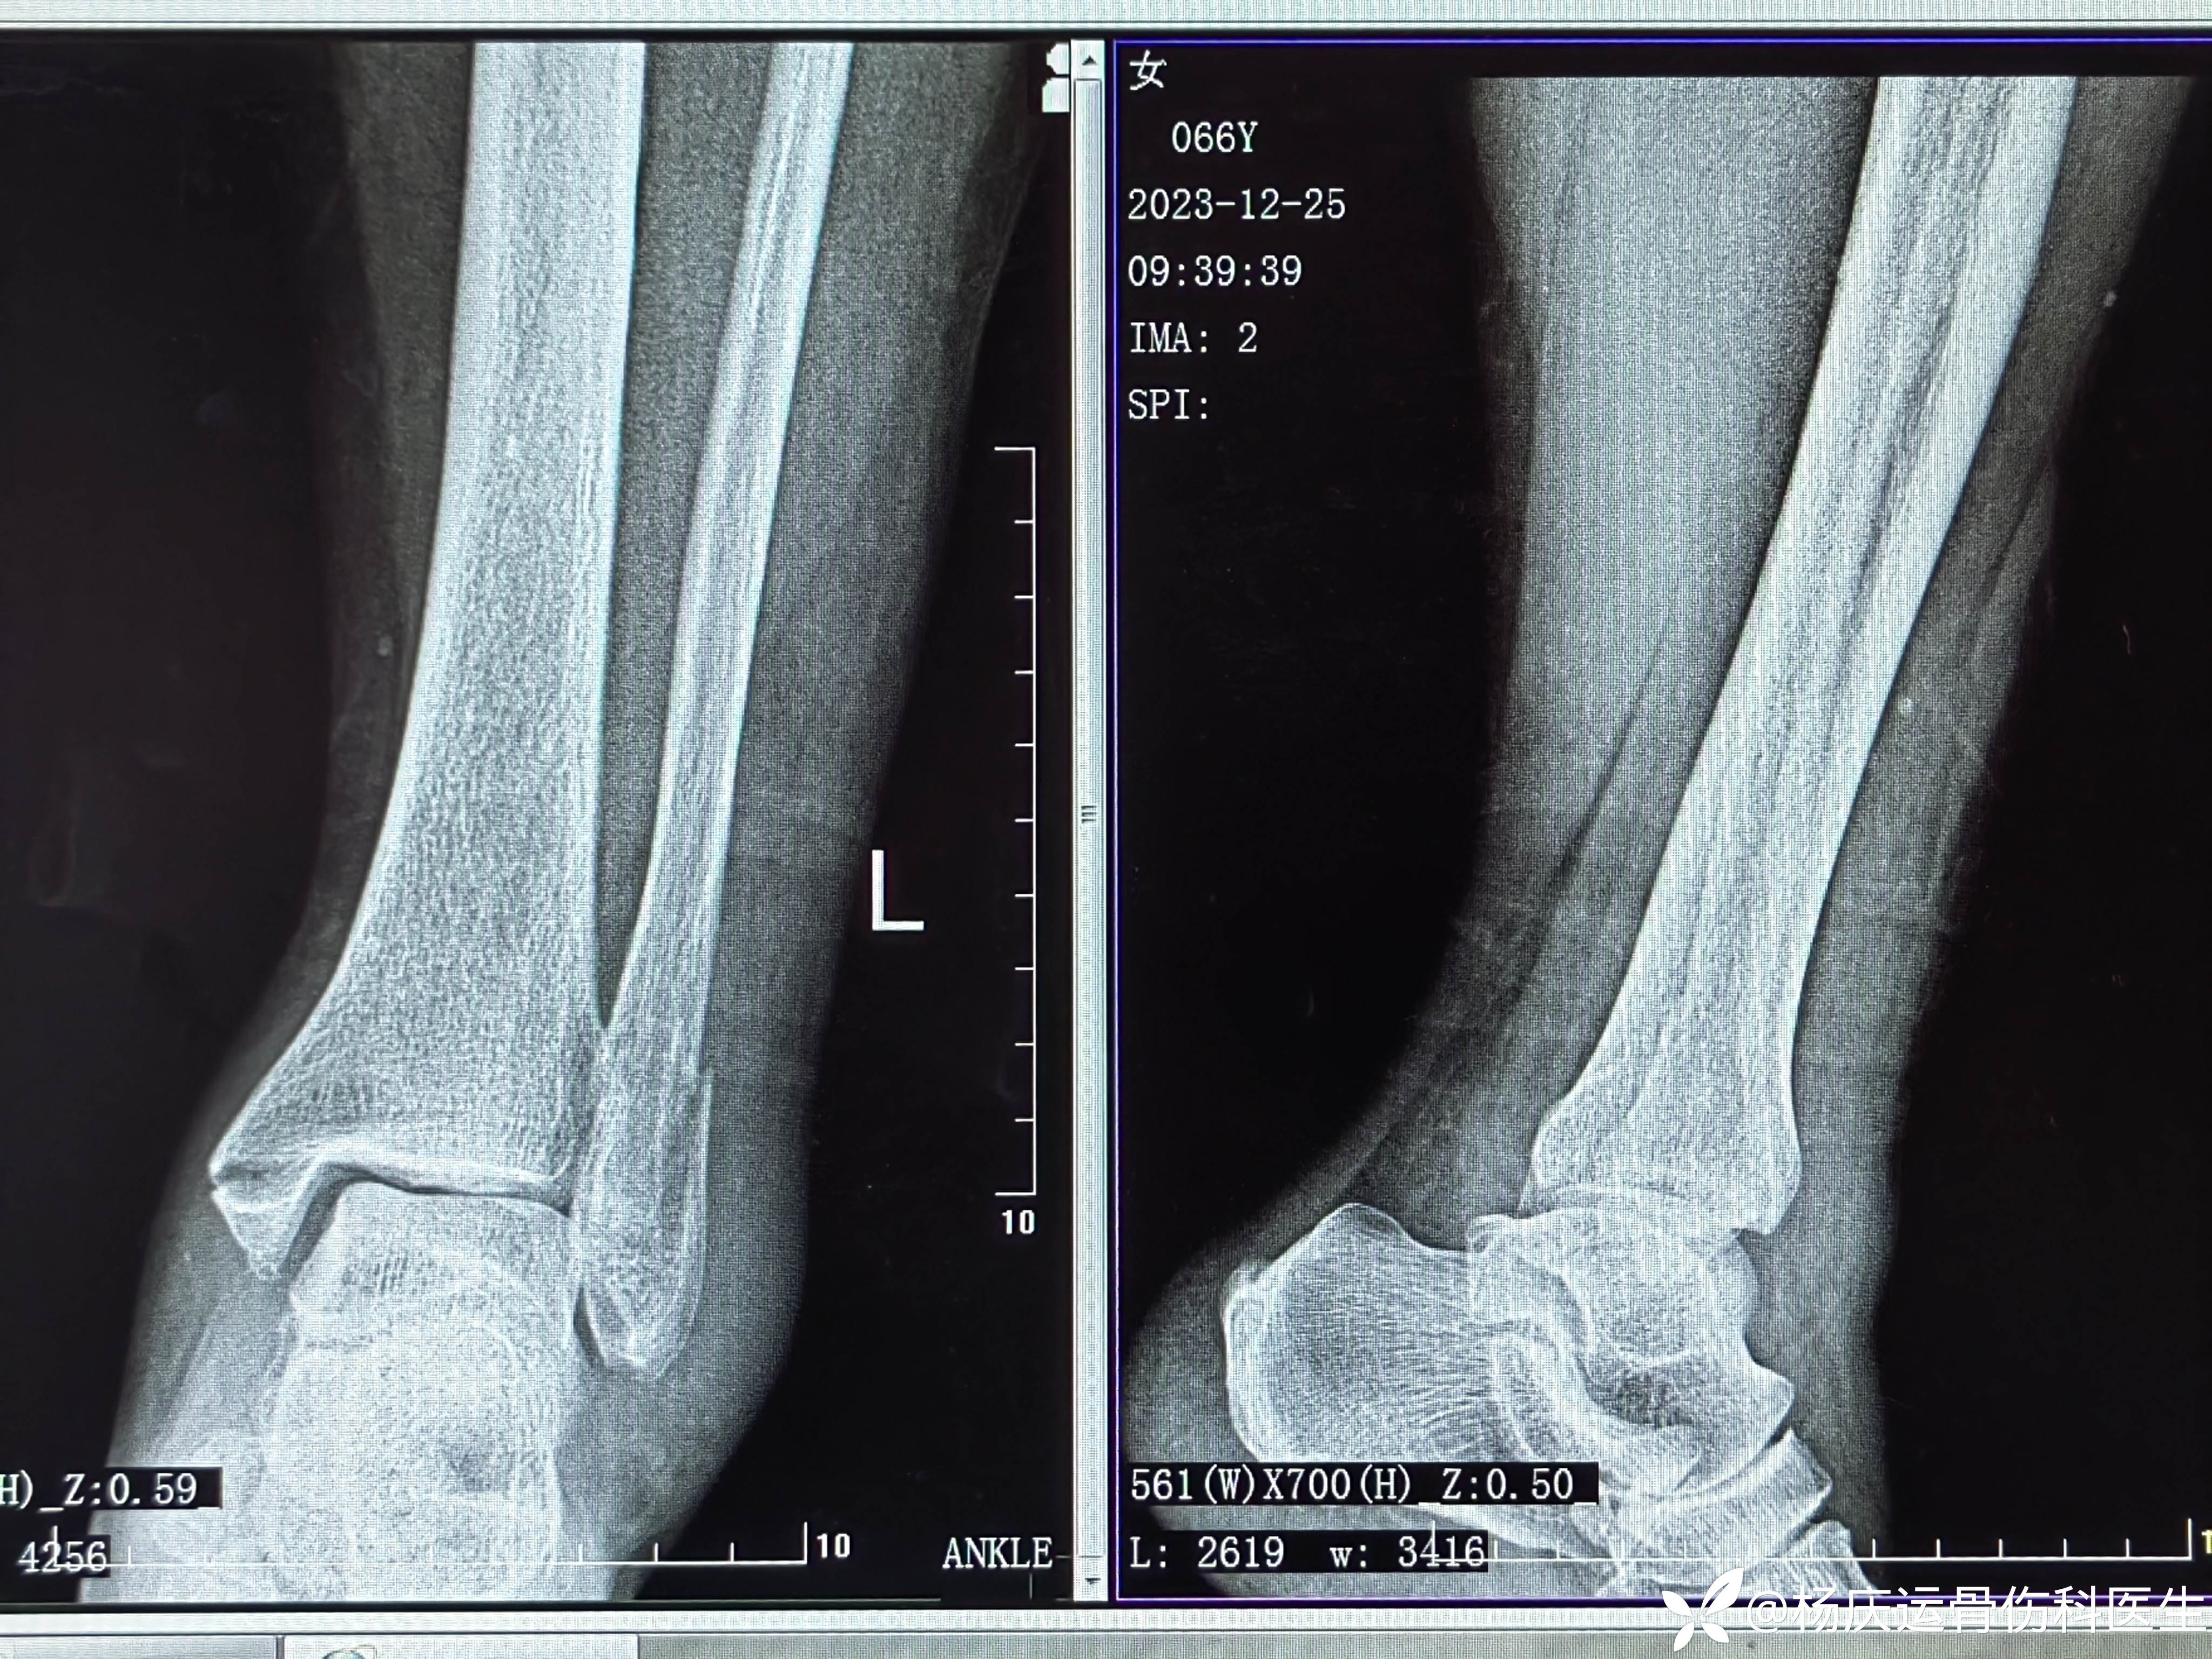

患者矫,女,66岁,左踝扭伤肿痛畸形2小时

初步诊断:左踝关节骨折(L-H分型:旋后外旋型IV)

首诊片

CT